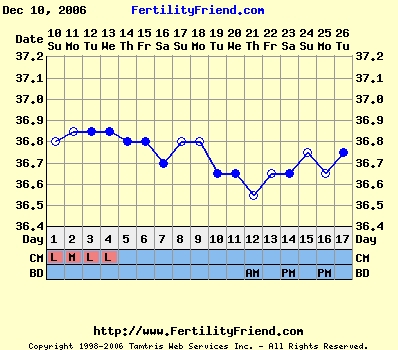

Nem tudom, hogy ez normális-e, miközben minden hormonom rendben, és a hőgörbe mutat pé-t. Meg van pozitív LH tesztem is...

Gaby: a Te görbéd elég cikkcakkos, szerintem később pé-zel...Végülis hathatott a párodnál már a gyógyszer, ha nem is drasztikusan, de már jobbak lehetnek az eredményei...